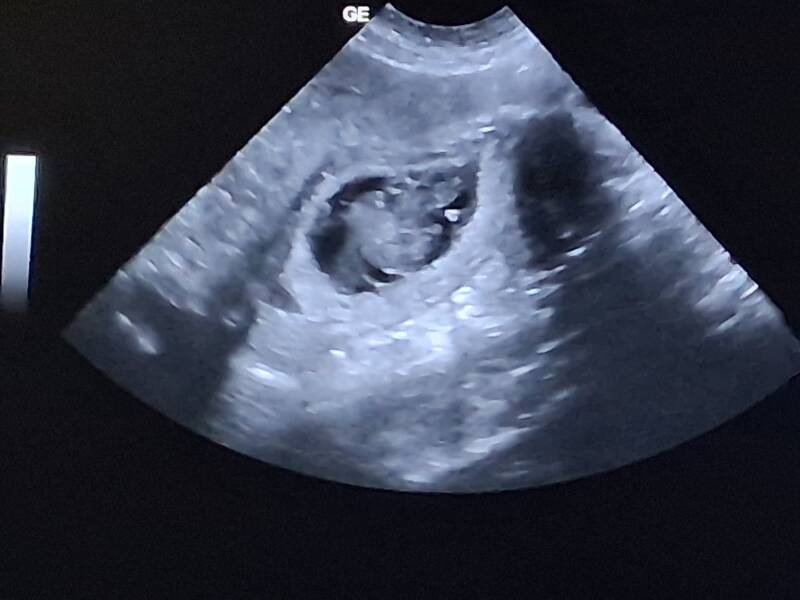

Juhu! Heute wurde die Trächtigkeit von Amari bestätigt.

Wir erwarten unsere Gumminäschen um den 20.2.26